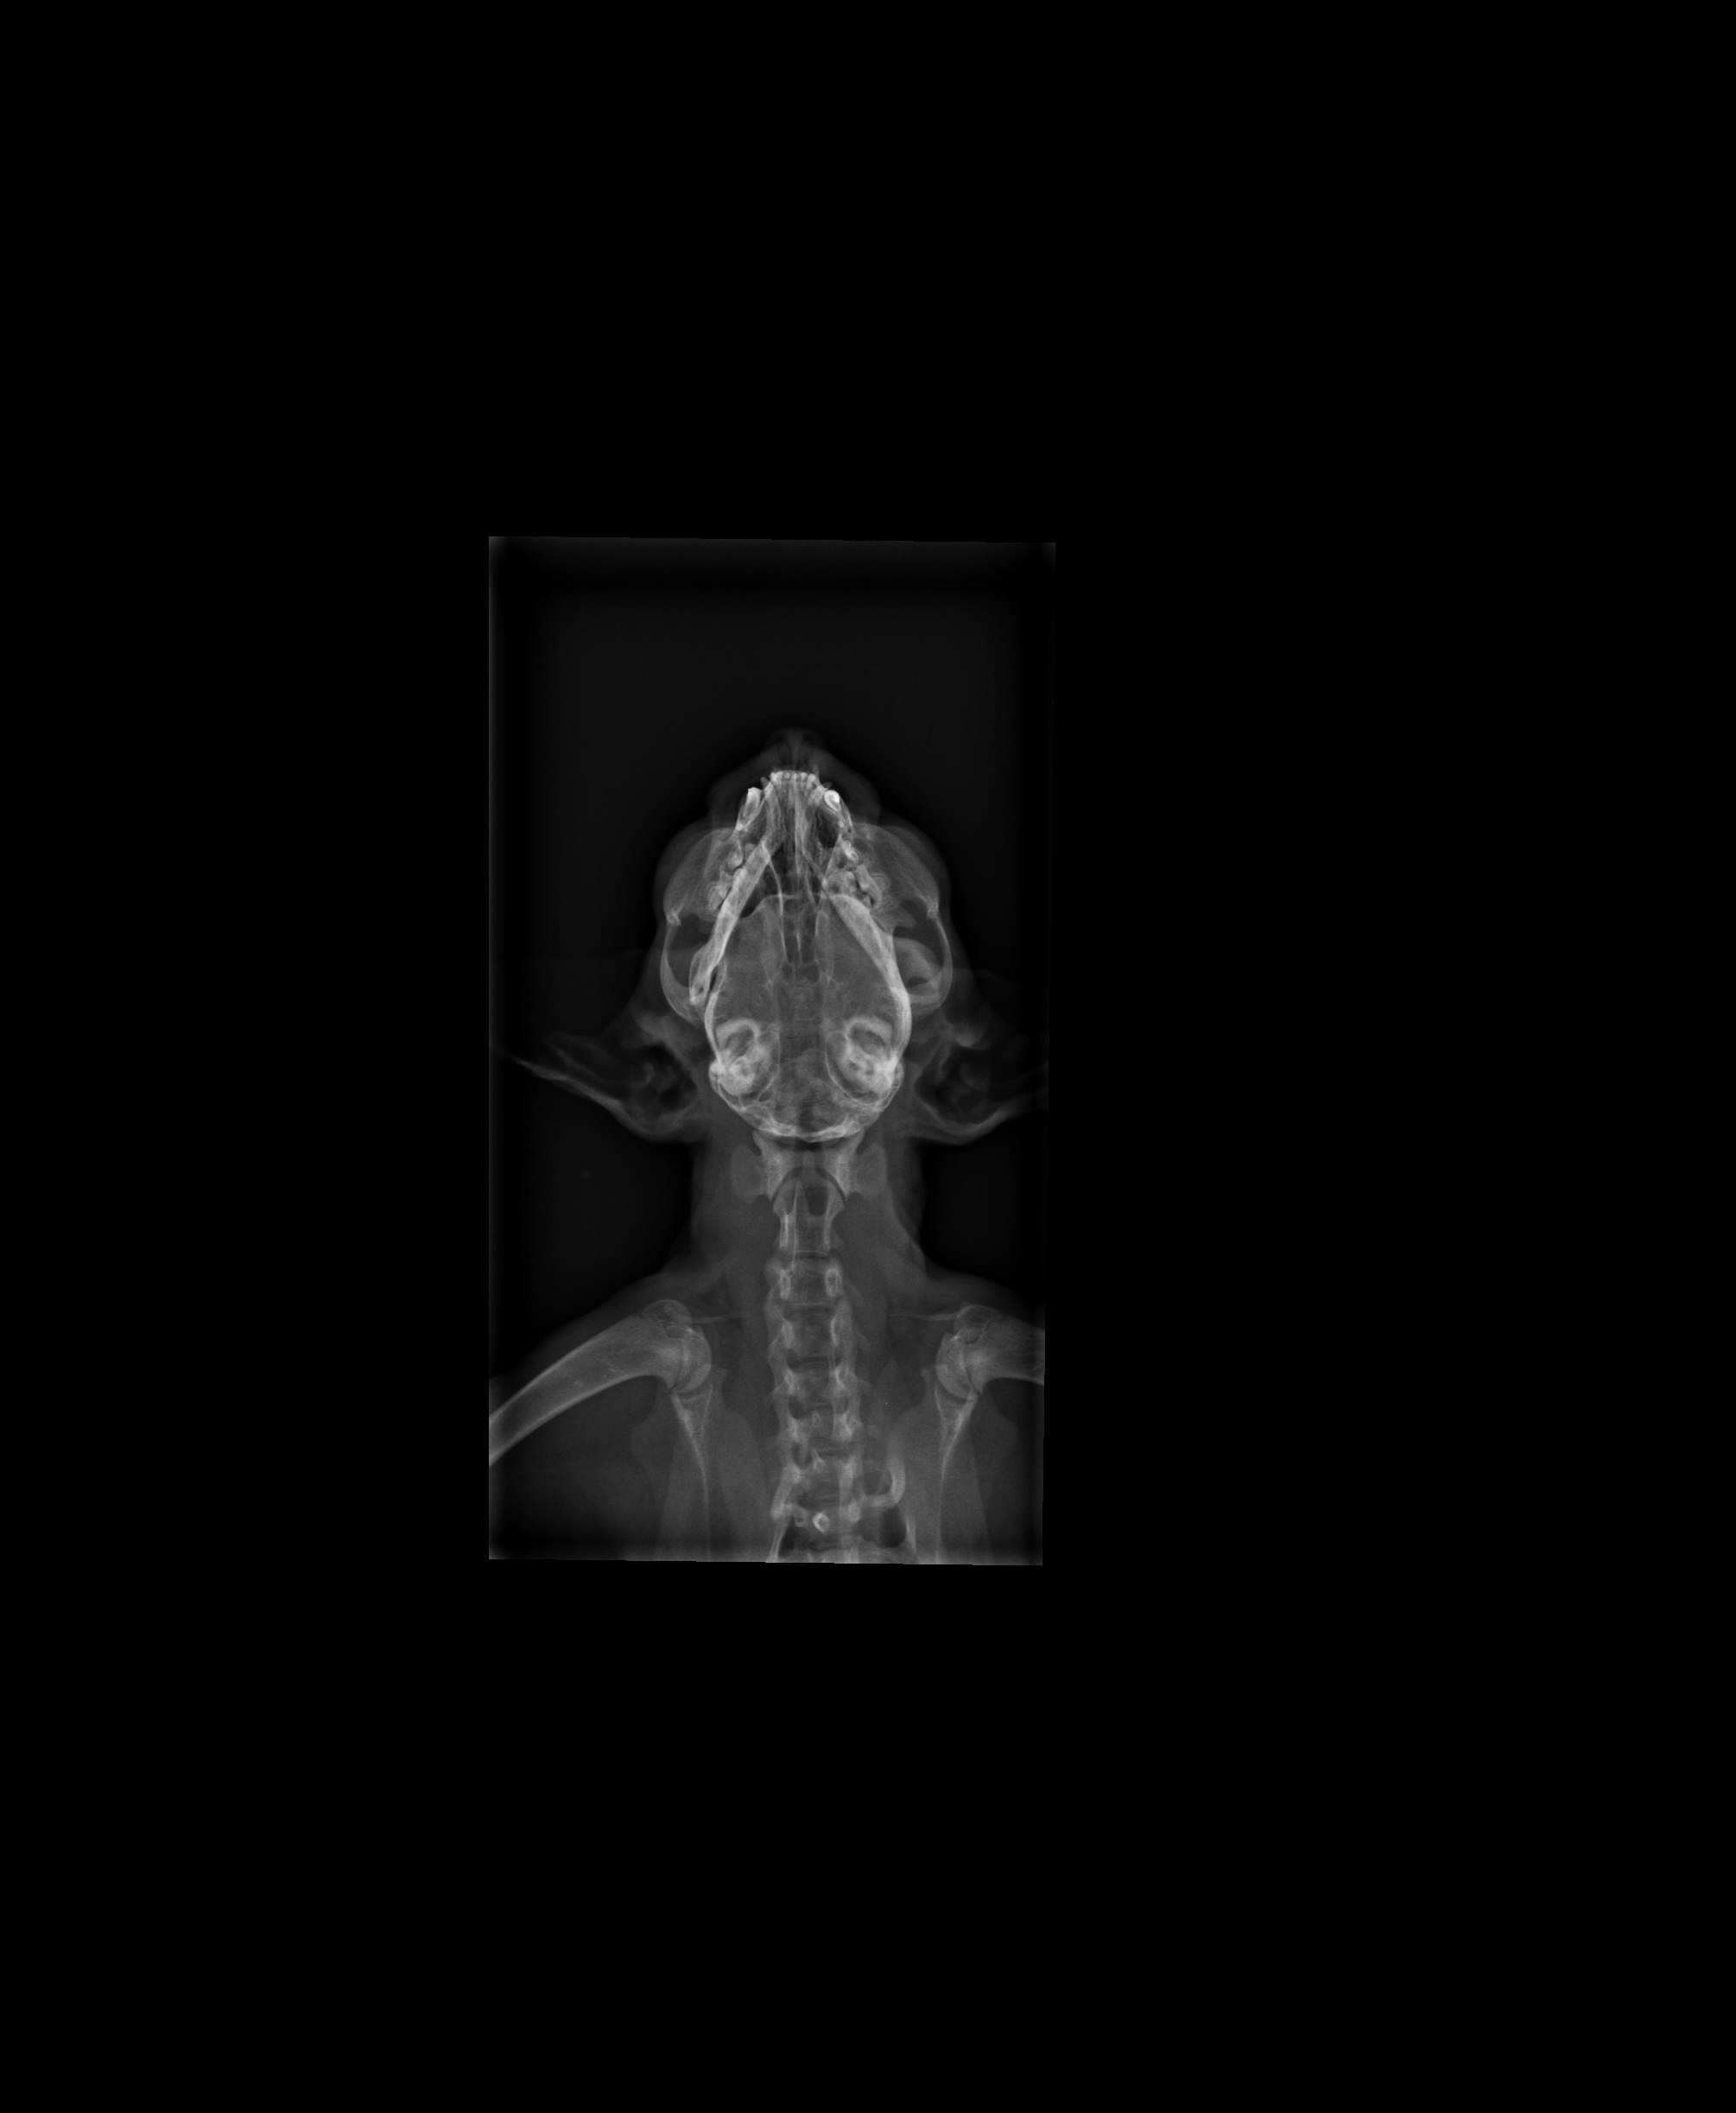

主題: 在地上打滾的貓咪 申請者姓名: 許秀青 花色: 申請日期: 2013-09-30 09:52:58 申請者部落格: 申請者臉書網址: 所在縣市/合作醫院: 高雄市/恩澤動物醫院 治療費用: 9550元 需求人數: 10人 已結案 (2014-01-10 17:59:06) 報名人員: Kim Meng(已付款)、ERic YU(已付款)、Patrick(已付款)、詩詩(已付款)、hero178(已付款)、紅色柚子(已付款)、Nix Lin(已付款)、吳毓軒(已付款)、SASA(已付款)、黃小歐(已付款)、 候補人員: 動物病情說明: 去公園溜狗時發現一隻在地上痙攣打滾的貓咪…因為颱風來了不忍心讓牠在公園淋雨所以趕緊送的杜專科做檢查醫療,檢查結果貓咪的眼睛已喪失功能,下巴有舊傷導致無法進食,有腦傷的現象 動物近況說明: 貓咪的眼睛確定喪失功能,現在嘴巴可以微張30度緩慢進食(雞肉泥或泡軟的乾糧),但走路無法保持平衡,貓咪的狀況無法原地野放,已接回家中照顧